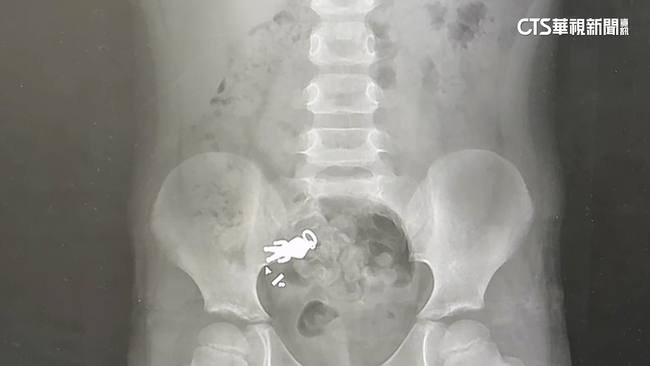

羅東博愛醫院小兒科主任謝錦桐說:「這是小朋友吞下去的這個超人形狀的吊墜。」這是小朋友吞下去的這個超人形狀的吊墜,X光影像中,一隻清晰可見的公仔,就藏在身體裡。

原來9月6日晚上,小朋友一邊看電視一邊吃餅乾,吃到一半說好像把玩具吃下肚了,等了兩天還是不見公仔身影,9月8日到醫院照X光果然發現公仔,叔叔將X光片PO上網,貼文吸引超過4萬人按讚,引發熱烈討論。

羅東博愛醫院小兒科主任謝錦桐說:「的確還在身體裡面,不過已經順利到達腸子的部分了,而且小朋友目前沒有任何症狀,那這個吊墜本身看起來,並沒有什麼尖銳的成分,看起來應該是可以順利排出的一個大小。」